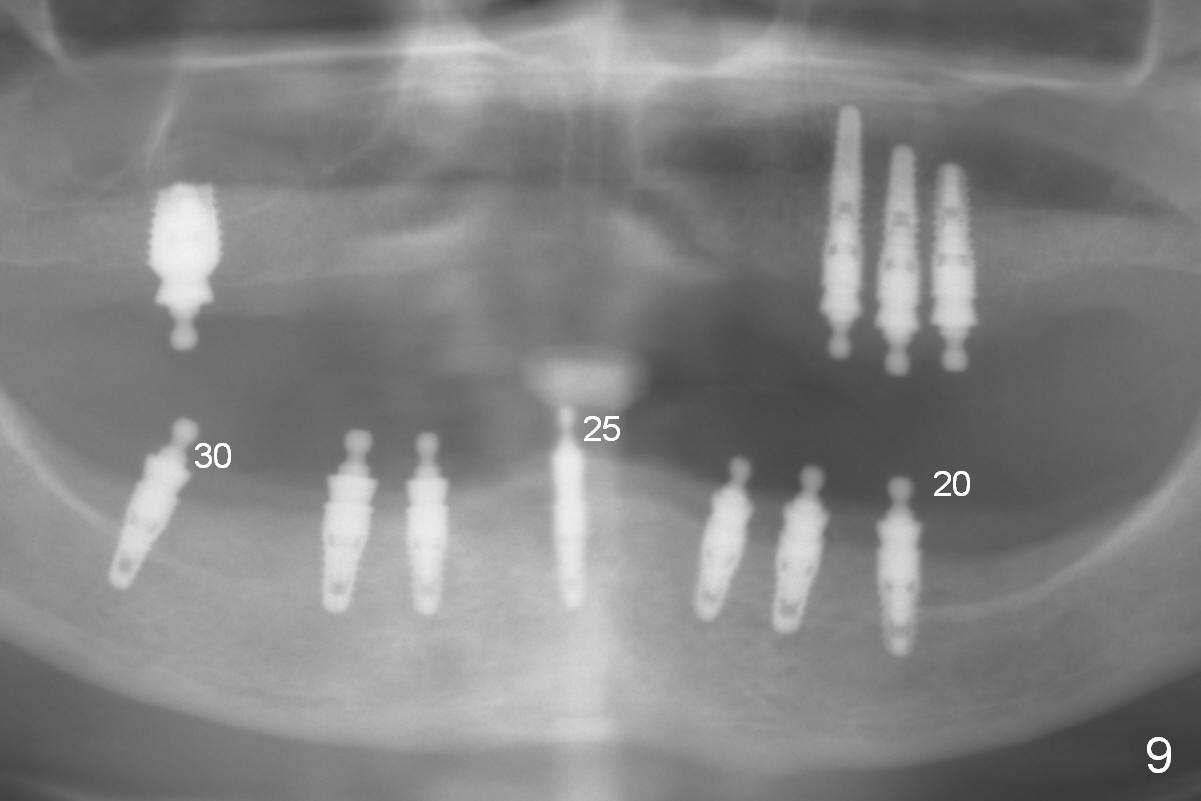

In the 2nd stage, three implants are placed at #20,25 and 30 (Fig.9).